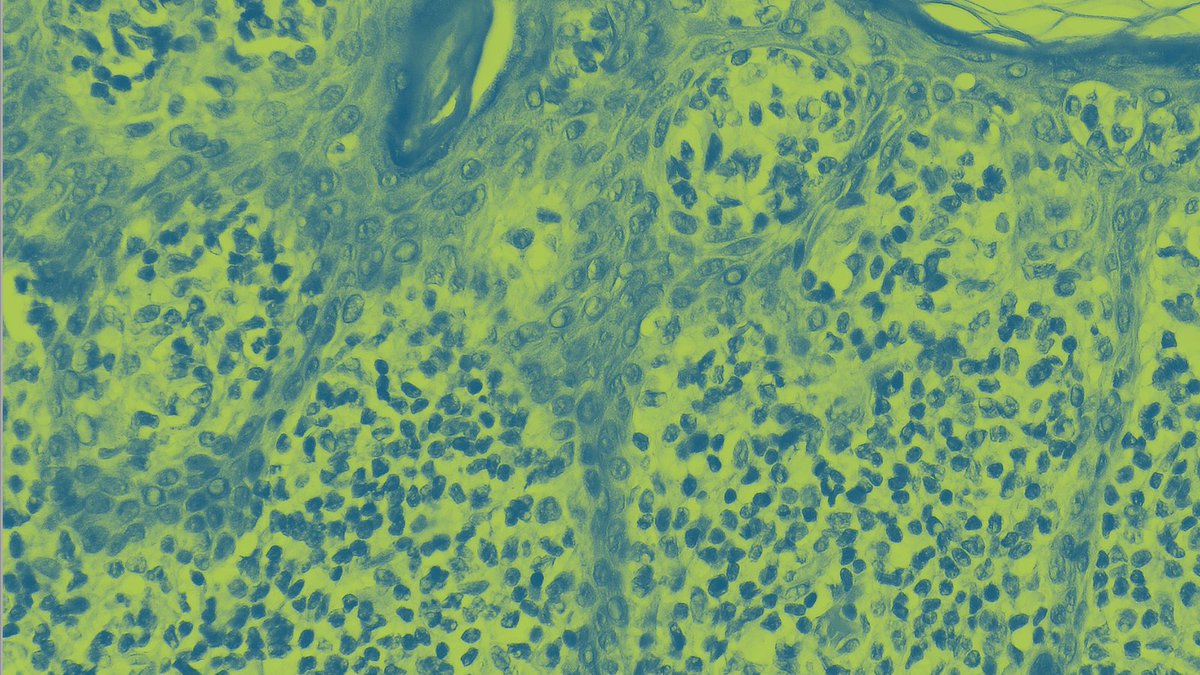

Die Klinik für #Dermatologie und das #Hautkrebszentrum #Lippe laden am 29.03.2023 interessierte Fachkräfte zum Detmolder #DermatoOnkologischen Nachmittag ein: klinikum-lippe.de/veranstaltung/…